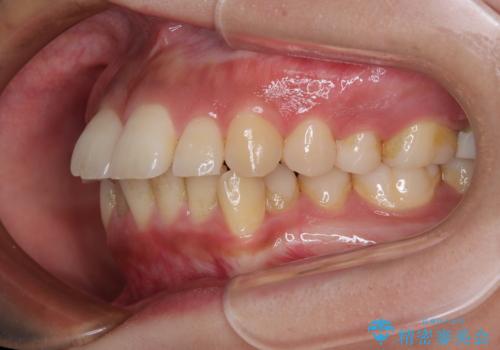

- 前歯のデコボコと口元の突出感を気にして来院された患者様です。

上下前歯がくちばしのように突出していたため、上下左右の第一小臼歯4本を抜歯し、ワイヤー装置にて矯正治療を行うこととしました。

口元の突出感が改善されてことで、下唇に引っかかっていた上顎前歯も気にならなくなりました。